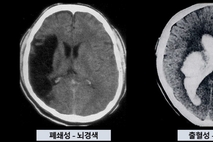

매번 MRI 찍는 대신…"간단 피검사로 뇌질환 경과확인 가능"

국내 연구진이 자기공명영상 촬영장치(MRI)를 대신해 혈액검사만으로 간단히 뇌 질환의 경과를 추적할 수 있는 나노기술 개발에 성공했다. 서울아산병원은 이 병원 신경과 이은재 교수와 의생명연구소 김진희 박사, 연세대학교 생명공학과 신용 교수 연구팀이 이 같은 연구 결과를 최근 도출했다고 11일 밝혔다. 서울아산병원에 따르면 대부분의 뇌 질환으로 인해 손상된 신경세포는 쉽게 회복되지 않아 이에 대한 조기 진단과 질병 활성도에 대한 모니터링이 중요하다. 그러나 뇌는 조직 검사가 힘들어 고비용 MRI를 반복 촬영해야 하는 데다가 영상 검사로는 미세한 변화를 정밀 추적하는 데 한계가 있다는 어려움이 있었다. 이에 연구팀은 먼저 특정 단백질의 구조를 모사해 표적 분자를 정밀하게 인식하는 '펩타이드 각인 나노복합체 기술'을 개발해 뇌와 척수에 존재하는 '성상교세포'만을 혈액에서 분리해냈다. 이후 연구팀은 서울아산병원 바이오뱅크에 보관된 혈청 시료 147개를 확보했다. 분석 대상에는 시신경척수염 스펙트럼 장애·다발성경화증·파킨슨병 등 환자의 혈청 시료와 건강한 이의 대조군 혈청이 포함됐다. 연구팀이 나노복합체 기술을 활용해 혈청 시료를 분석한 결과, 성상교세포 손상을 반영